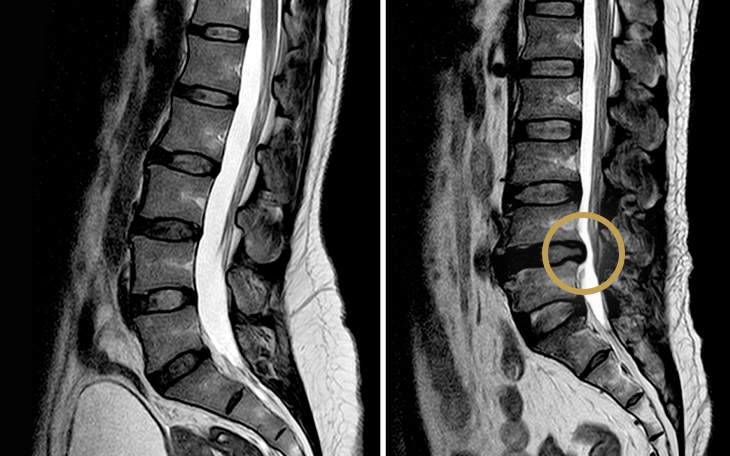

Röntgenaufnahmen können eine verminderte Bandscheibenhöhe zeigen, was die Diagnose DDD bestätigt. Ein MRT wird häufig empfohlen, um zusätzliche Erkrankungen wie einen Bandscheibenvorfall oder eine Spinalkanalstenose zu erkennen, die das Behandlungskonzept beeinflussen könnten. Zudem kann mit der MRT das Ausmaß und die Aktivität der degenerativen Veränderungen beurteilt werden.

Einfache Röntgenbilder zeigen keine Spinalkanalverengung, da sie nur Knochenstrukturen abbilden. Sie können jedoch auf begleitende Arthrose hinweisen. Die Methode der Wahl ist die Magnetresonanztomografie (MRT), mit der sich Ausmaß und Lokalisation der Einengung genau darstellen lassen – ohne Strahlen oder Kontrastmittel.

Ein MRT wird eingesetzt, um Nervenkompressionen zu beurteilen. Das MRT kann anzeigen, ob ein Bruch neu (aktiv) oder alt ist (chronisch).

Ein einfaches Röntgenbild der Wirbelsäule zeigt nur die Knochenstruktur, nicht jedoch die Bandscheiben oder Nerven. Für eine exakte Diagnose wird daher ein MRT (Magnetresonanztomographie) empfohlen. Es ist nicht-invasiv und zeigt die betroffene Bandscheibe deutlich. Vor der Verfügbarkeit des MRT wurden CTs oder Myelogramme genutzt. Bei Patienten mit Herzschrittmachern, die kein MRT machen dürfen, müssen diese Verfahren weiterhin eingesetzt werden.